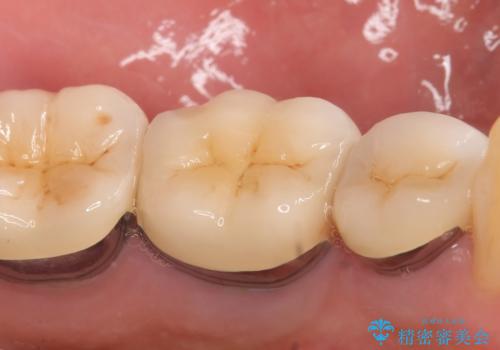

その後症状の消失を確認し、オールセラミッククラウンによる補綴を行いました。

今回用いたオールセラミッククラウンはジルコニアフレームという白い素材の上にセラミックを盛っているため、審美性が非常に高いのが特徴です。

また、ジルコニアは人工ダイヤモンドの材料にも使われているほど高い強度を持っており、そのためオールセラミッククラウンは審美性だけでなく、奥歯やブリッジの補綴も可能とするクラウンです。